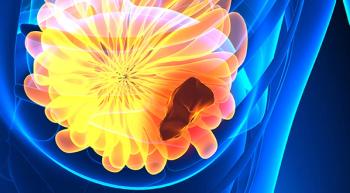

A new study shows that using the targeted agents lapatinib (Tykerb) and trastuzumab (Herceptin) together, combined with an aromatase inhibitor (AI), significantly reduced the risk of death or progression in women with HER2-positive/HR-positive metastatic breast cancer compared with each single targeted agent in combination with an AI.

The combination of olaparib (Lynparza) and durvalumab (Imfinzi) for pretreated patients with germline BRCA-mutated (gBRCAm), HER2-negative metastatic breast cancer shows great promise for future treatment.

The FDA has approved the combination of pertuzumab (Perjeta), trastuzumab (Herceptin) and chemotherapy as an adjuvant treatment for patients with HER2-positive early breast cancer at high risk for recurrence.

This PARP inhibitor therapy is more effective than chemotherapy in extending progression-free survival and reducing risk of death from BRCA-positive breast cancer.

Shortening the intervals between chemotherapy cycles or administering the drugs sequentially compared to current techniques reduces early-stage breast cancer recurrence and mortality, study shows.

Trastuzumab (Herceptin) biosimilar MYL-1401O (Ogivri; trastuzumab-dkst), which is co-developed by Mylan and Biocon, has just been approved by the FDA for HER2-positive patients with breast cancer or metastatic gastric or gastroesophageal junction adenocarcinoma, the same indications as trastuzumab.